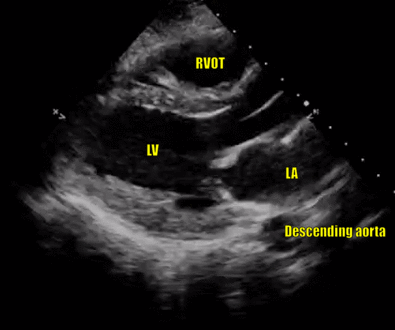

name the view

Left parasternal long axis